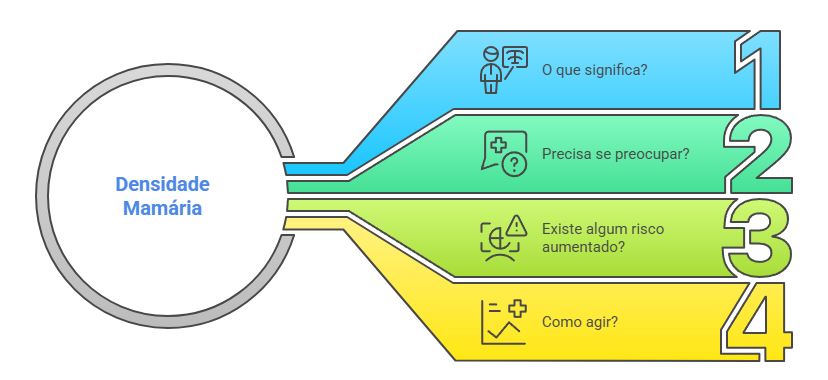

Você acabou de receber o resultado da sua mamografia e se deparou com o termo “mamas densas”? Essa informação, muitas vezes inesperada, pode gerar ansiedade e uma série de questionamentos. Afinal, o que isso significa? Você precisa se preocupar? Existe algum risco aumentado?

Tranquilize-se. Neste artigo, vou esclarecer tudo sobre densidade mamária de forma simples para que você entenda exatamente o que isso representa e como agir para manter sua saúde mamária em dia.

O Que São Mamas Densas?

Primeiro, quero deixar bem claro: mamas densas representam apenas uma variação anatômica normal das mamas. Não são uma doença nem uma anomalia.